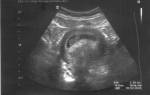

Аппарат УЗИ (ультразвукового исследования) позволит установить наличие/отсутствие сердцебиения, понять нормально ли развивается плод, соответствует ли его размер сроку беременности.

Стоит отметить, что благодаря УЗИ можно увидеть голову ребенка, его движения, желточный мешок. Обязательным является фиксация веса будущей мамы, пока еще он не прибавляется, но именно с этого дня начинается пристальное наблюдение за этим показателем.

На 8 неделе размер плода можно сравнить с черешней. На УЗИ специалист увидит движение конечностями, которые он совершает. Плод увеличивается каждые сутки на 1 мм.